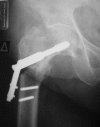

This study is a randomized prospective study comparing two fracture fixation implants, the extramedullary sliding hip screw (SHS) and the dual lag screw cephalomedullary nail, in the treatment of intertrochanteric femoral fractures in the elderly. One hundred and sixty-five patients with low-energy intertrochanteric fractures, classified as AO/OTA 31A, were prospectively included during a 2-year period (2005-2006). Patients were randomized into two groups: group A included 79 hip fractures managed with sliding hip screws and group B included 86 fractures treated with cephalomedullary nails. Delay to surgery, duration of surgery, time of fluoroscopy, total hospital stay, implant-related complications, transfusion requirements, re-operation details, functional recovery, and mortality were recorded. The mean follow-up was 36 months (24-56 months). The mean surgical time was statistically significantly shorter and fluoroscopy time longer for the group B. No intraoperative femoral shaft fractures occurred. There was no statistically significant difference in the functional recovery score, reoperation, and mortality rates between the 2 groups. A new type of complication, the so-called Z-effect phenomenon, was noticed in the cephalomedullary nail group. There are no statistically significant differences between the two techniques in terms of type and rate of complications, functional outcome, reoperation and mortality rates when comparing the SHS and the cephalomedullary nail for low-energy AO/OTA 31A intertrochanteric fractures. Our data do not support recommendations for the use of one implant over the other.